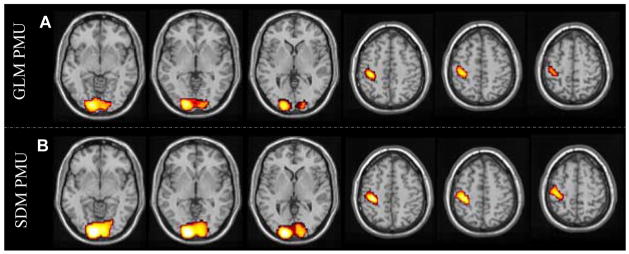

SDM PMU and GLM PMU

Fig. 10 shows the suprathreshold pseudo-t (Nichols and Holmes, 2002) maps of GLM PMU and SDM PMU. Using the same threshold (P < 0.05, FWE corrected, corresponding to pseudo-t > 5.8), this figure clearly demonstrates that SDM PMU (Fig. 10B) produced larger suprathresholded clusters. Table 2 lists the result statistics of GLM PMU and SDM PMU. Consistent with Fig. 10, SDM PMU yielded higher peak pseudo-t values, larger suprathresholded clusters, and higher mean pseudo-t values. Additionally, the suprathreshold cluster of SDM PMU in visual cortex demonstrated higher significance using cluster-wise permutation than that of GLM PMU, while the cluster of SDM PMU in motor cortex presented the same cluster-wise permutation significance.

Figure 10.

Suprathresholded group level permutation pseudo-t maps of A) GLM PMU and B) SDM PMU. The threshold is P < 0.05 (FWE corrected, corresponding to pseudo-t > 5.8), and the display window is 0 ~ ±10.

Table 2.

Peak pseudo-t values, cluster extensions and within-ROI averaged pseudo-t values of SDM PMU and GLM PMU. “peak”, “ext”, “mean”, and “cluster P” represent “peak pseudo-t”, “extension of the suprathresholded cluster”, “within ROI average pseudo-t”, and “P value of the suprathresholded cluster using FWE correction”, respectively.

| Methods | Visual cortex | Motor cortex | ||||||

|---|---|---|---|---|---|---|---|---|

| peak | ext | mean | cluster P | peak | ext | mean | cluster P | |

| SDM PMU | 12.49 | 1810 | 6.7 | 0.001 | 10.15 | 538 | 5.9 | 0.001 |

| GLM PMU | 9.56 | 1126 | 5.5 | 0.001 | 8.67 | 339 | 5.1 | 0.002 |